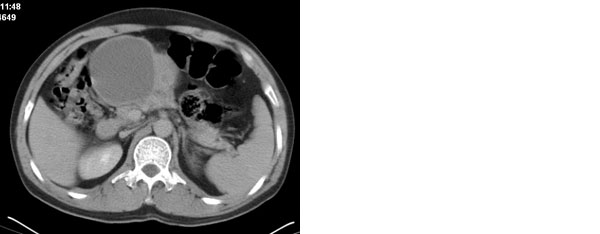

李**,男,46岁,便血1天入院,慢性贫血貌,腹平、软,剑突下压痛,肠鸣音稍活跃,hb大于1g/l,胃镜:慢性浅表性胃炎,b超:1肝内多发性占位 2腹腔内囊性肿块 ,肝内圆形影平扫ct值42.9,动脉期48.6,静脉期58.2,延迟期62.2

影像学表现:1 腹腔前中部、胰腺前方囊实性病灶(个人认为确定有否实性成分存在这是关键,涉及到鉴别诊断,如果是口服阳性造影剂则可明确左侧是不是小肠了),囊性部分囊壁不均,实性部分有强化,与小肠关系较密切,局部小肠受推移;与胰头、胃后壁均有脂肪间隙存在;2 胰腺无异常改变,胰周无渗出;3肝后段包膜下2个小圆形低密度灶,从图像和楼主提供的ct值来看有轻度强化,灶周无片状强化,不似单纯囊肿及肝癌、炎性病变表现;4 腹膜后及腹腔内无淋巴结肿大。

胰腺边界清晰,胰周筋膜不厚,胰周脂肪密度无明显增高;其前方囊实性病灶,边界清晰,增强后实性部分轻度强化;肝内多发边界清晰低密度影,增强后无明显强化(平扫ct值42.9,动脉期48.6,静脉期58.2,延迟期62.2)。

原因:胰头前方,前上腹部巨大囊实性肿物,与小肠关系密切,与胰头及胃壁之间脂肪间隙存在,囊壁不均匀,部分强化,占位效应明显,小肠上段扩张,十二指肠及胃腔内大量食物存留,说明上消化道有部分梗阻。因此,考虑来源于肠道的肿瘤。再结合其病史及肝内改变,这样考虑更有道理。